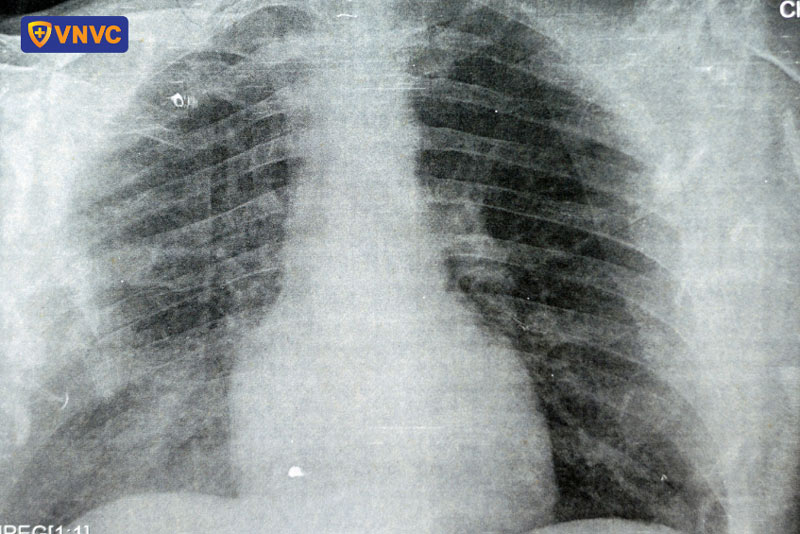

Đây là một thách thức lớn đối với ngành y tế, đòi hỏi sự nghiên cứu và phát triển các phương pháp điều trị hiệu quả hơn. Nếu không được phát hiện và điều trị kịp thời, đúng cách, zona có thể dẫn đến hàng loạt biến chứng khác như nhiễm khuẩn, tổn thương mắt tăng nguy cơ mù lòa vĩnh viễn, viêm não, viêm màng não, viêm phổi, viêm cơ tim, đột quỵ... có khả năng gây tử vong.

Xét nghiệm PCR hoặc nuôi cấy virus cũng có thể được chỉ định để xác nhận chẩn đoán, đặc biệt trong những trường hợp khó khăn hoặc cần loại trừ bệnh lý khác. Chẩn đoán hình ảnh như MRI hoặc CT scan thường không cần thiết trừ khi có nghi ngờ biến chứng thần kinh nghiêm trọng.